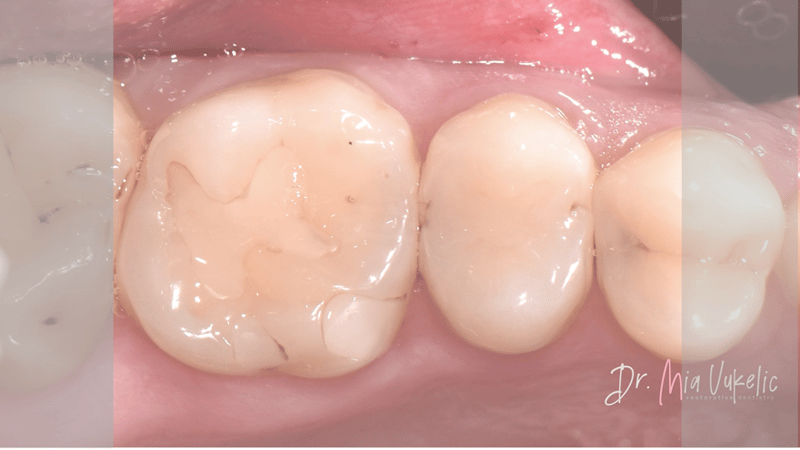

The patient visited the clinic for an annual check-up. Following a clinical and radiographic examination, a secondary carious lesion was diagnosed on occlusal surface of tooth 26 and two additional carious lesions on the distal surfaces of teeth 24 and 25. The patient reported no specific symptoms. The prescribed treatment involves the placement of a Class I restoration on tooth 26 and Class II restorations on teeth 24 and 25.

![]() |